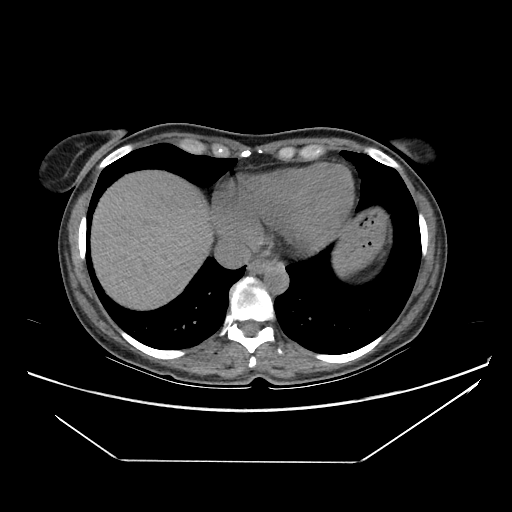

Image Grid

4Γ—3 grid: Rows show different image types (Original NATIVE, Reconstructed NATIVE, Original VENOUS, Generated VENOUS), Columns show windowing techniques (No Window, Lung Window, Mediastinum Window)

Original NATIVE CT scan (input)

Full window (WL 1023.5, WW 4095 β†’ Low βˆ’1024, High +3071)

Original VENOUS CT scan

Generated VENOUS CT scan (A→B translation)